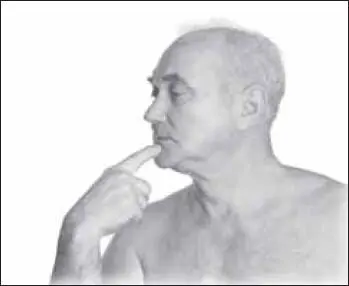

Следующая точка – чэн-цзянъ (она расположена под нижней губой во впадине, находящейся в центре подбородочной ямки) (рис. 137).